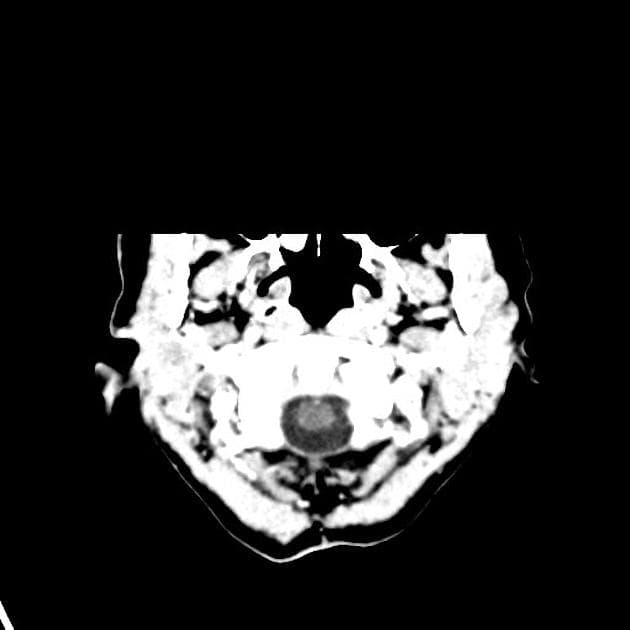

Phát hiện nhiều nốt (nodule) ở nhu mô não vùng đại não (cerebrum) và tiểu não (cerebellum), cả hai bên, trong đó tổn thương lớn nhất nằm ở thùy thái dương phải (temporal lobe), kích thước khoảng 17 × 16 mm.

Có phù vận mạch (vasogenic edema) quanh tổn thương. Tổn thương có tín hiệu không đồng nhất (heterogeneous signal intensity): chủ yếu giảm tín hiệu (hypointense) trên hình ảnh T1W, tăng tín hiệu (hyperintense) trên T2W và FLAIR, kèm theo hạn chế khuếch tán nhẹ (mild diffusion restriction).

Trên hình ảnh SWI, thấy các vùng giảm tín hiệu (hypointensities) rải rác, tương ứng với tăng tín hiệu trên hình ảnh pha (Phase imaging) – gợi ý xuất huyết (suggestive of haemorrhage).

Sau tiêm thuốc cản quang, tổn thương cho thấy tăng quang mạnh, không đồng nhất (strong, heterogeneous enhancement).